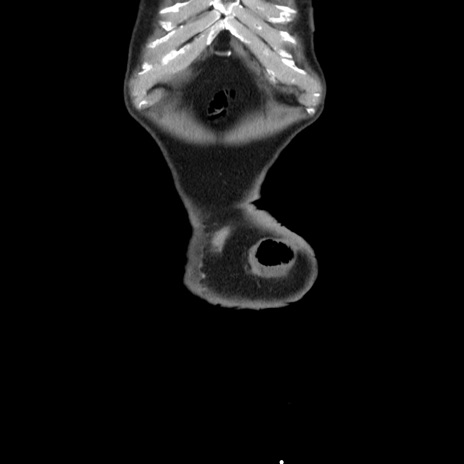

症例24(冠状断像)

横断像